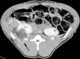

Air from retrograde pyelogram

May Cause

Urinary tract gas